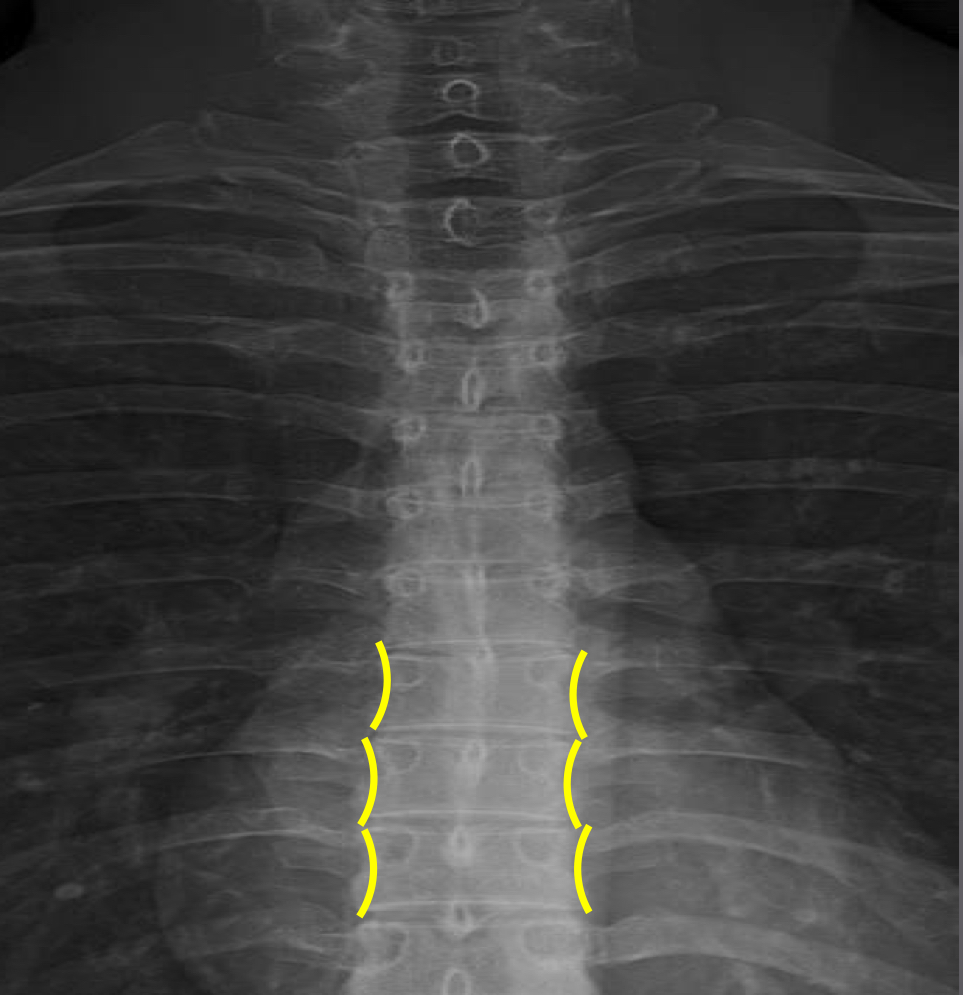

What view is this?

AP (Anterior to Posterior) Thoracic

What is this?

Junction of Laminae

What is this?

Pedicle Shadows

What is this?

Vertebral Waist

What is this?

Inferior Endplate Tips

What is this?

Superior Endplate Tips

What is this?

Disc Spaces